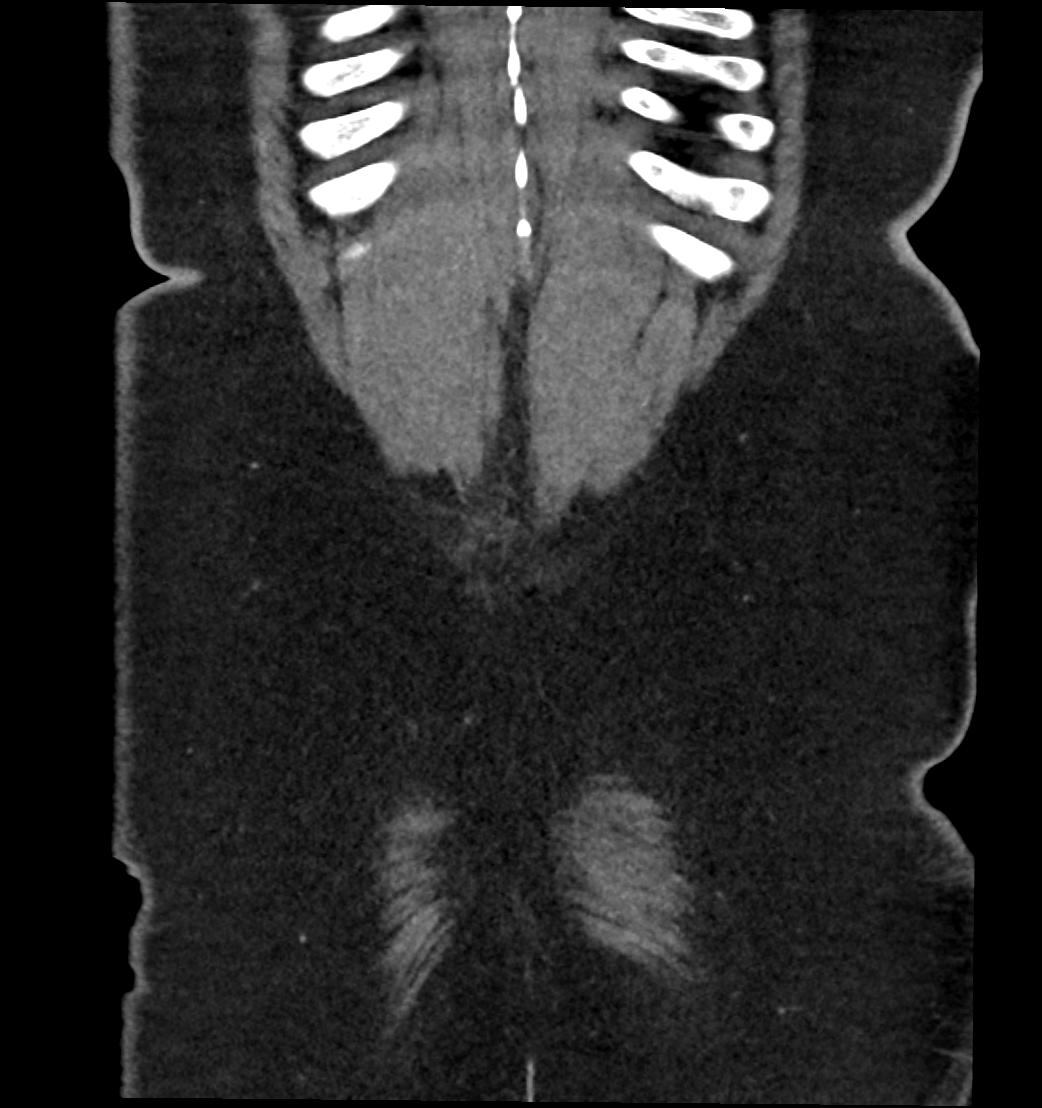

Patient: Padmakumar A. , *1988-04-24, PID: 3000069741773230809

Study Description: CT ABDOMEN

Image Series: Abdomen Cor 3mm [4]